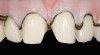

The pretreatment situation.

Figure 13

A patient in her 60s wanted to improve her smile but declined orthodontic treatment in favor of porcelain veneers (Figure 13). However, addressing her 8-mm pocket was the first step. The practitioner created biologically clean root surfaces using ultrasonic open-flap debridement, finishing burs, and manual tool instrumentation. Next, a mineralized freeze-dried bone allograft saturated in platelet-derived growth factor (Figure 14) using chemotaxis pulled the stem cells capable of regeneration into the site where repopulation was needed. Prior to closure, a resorbable membrane, polylactic acid-guided tissue regeneration—known for periodontal regeneration—was used (Figure 15). At 10 weeks, adequate healing had occurred. The patient at 6 and 10 weeks showed continued healing. Although some postoperative recession was evident, probing depths were less than 2 mm, and the patient was referred back to the restorative dentist for restorative therapy. As of this writing, she has not lost any teeth and is periodontally stable (Figure 16).